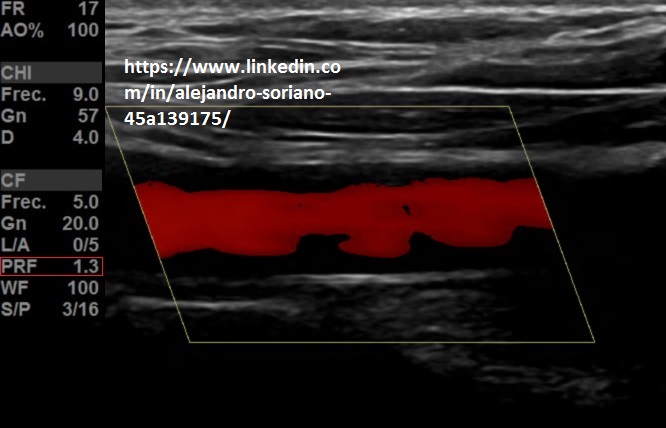

Se coloca un ROI que se superpone a la imagen 2D dándonos a conocer la distribución de los vasos respecto al tejido. Nos permite conocer la velocidad promedio del volumen de la muestra y su dirección.

Está establecido que los flujos que se aproximen a la sonda tengan colores rojizos, mientras que los que se alejan son colores azulados.

Es muy útil para el estudio de los vasos, pero vital para conocer la vascularización de estructuras sospechosas de patología, desde tendinopatías hasta lesiones tumorales.

- Frecuencia de repetición de pulsos (PRF) o escala de velocidades: la modificaremos en función del flujo que estemos estudiando; para flujos de alta velocidad la aumentamos para evitar “aliasing”; para bajos flujos la disminuiremos para tener mayor sensibilidad.